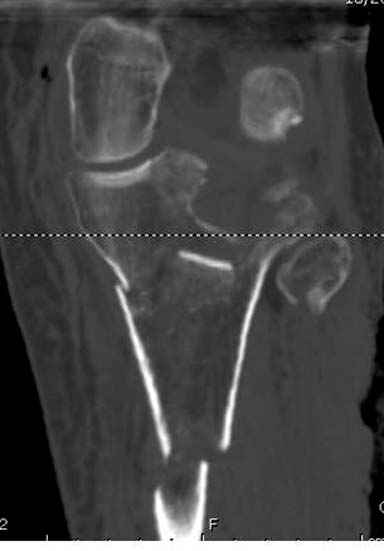

Если там действительная импрессия, пустое место без структуральных заполнителей, кость или синтетические материалы, не восстановится, а образуется коллапс, и ось конечности поведет после нагрузки. Кроме того там возможно "болт стяжка"?, в медиальной стороне выступает за кортекс, можно было укоротить! Потом создается впечатление, что не соответствуют мыщелки большеберцовой и бедренной костей? Покажите снимок.

Ваша упорство с минимальными данными защищаться забавляет, и пока не все убедились в Вашей правоте. Для нормальной защиты необходимы аргументированные доказательства исследованиями. КТ сканы и прицельно сделанные снимки коленного сустава, а так все аргументы - не более чем "моя фиксация, мне нравится". Без этих доказательств пока только Ваше упорство.....

Здесь пару случаев для сравнения,...в первых 1-4 слайдах метод фиксации одним фиксатором, как видно после 8 месяцев сохранилась ось. С 5 по 9 вариант двумя пластинами...